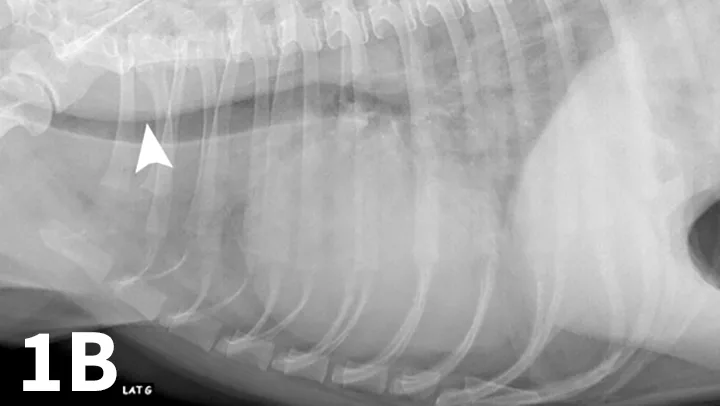

Ventrodorsal (A) and left and right lateral (B, C) thoracic radiographs of a 10-year-old West Highland white terrier showing a redundant tracheal membrane (1B, arrowhead; 1C, arrowhead), a severe generalized bronchointerstitial pattern, and a pleural fissure line (1A, arrow) between right pulmonary lobes.

Serum chemistry panel and CBC results were within range except for alkaline phosphatase (280 IU/L; range, 27-74) and hematocrit (57%; range, 37%-55%). Thoracic radiographs showed a severe bronchointerstitial pattern, right cardiomegaly, and prominent pulmonary artery trunk (Figure 1).